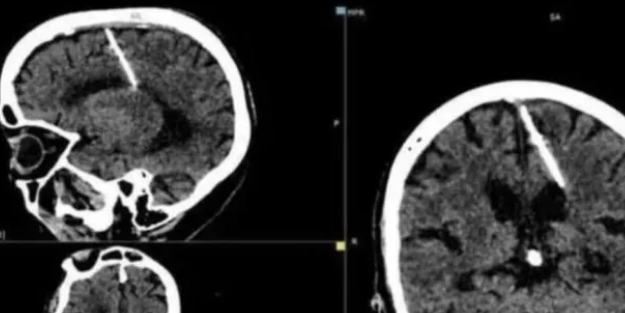

Rusya'nın Sakhalin bölgesinden 80 yaşındaki bir kadın, çektirdiği taramadan sonra beyninin sol tarafına 3 cm'lik metal bir iğnenin saplandığını keşfetti. Kadının tomografi sonuçlarının fotoğrafları yakın zamanda bölgenin sağlık bakanlığı tarafından şok edici bir açıklamayla birlikte yayımlandı.

Doktorlar, kadının yaşını göz önünde bulundurarak iğnenin, doğumundan hemen sonra kendi ebeveynleri tarafından beynine yerleştirildiğine inanıyor.